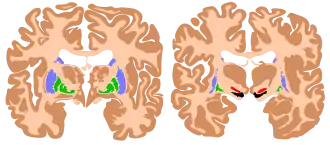

Au sens purement anatomique ils comprennent quatre noyaux pairs :

- le noyau caudé ;

- le noyau lenticulaire correspondant au putamen et au pallidum ;

- le noyau sous-thalamique ;

- la substance noire.

- le striatum composé du noyau caudé et du putamen (correspondant à la partie latérale du noyau lenticulaire) ;

- le globus pallidus interne (GPi) et le globus pallidus externe (GPe), correspondant au pallidum (partie médiale du noyau lenticulaire) ;

- le noyau sous-thalamique (ou corps de Luys) ;

- la substance noire compacte (SNpc, du latin : substantia nigra pars compacta), et la substance noire réticulée (SNr, substantia nigra pars reticulata).